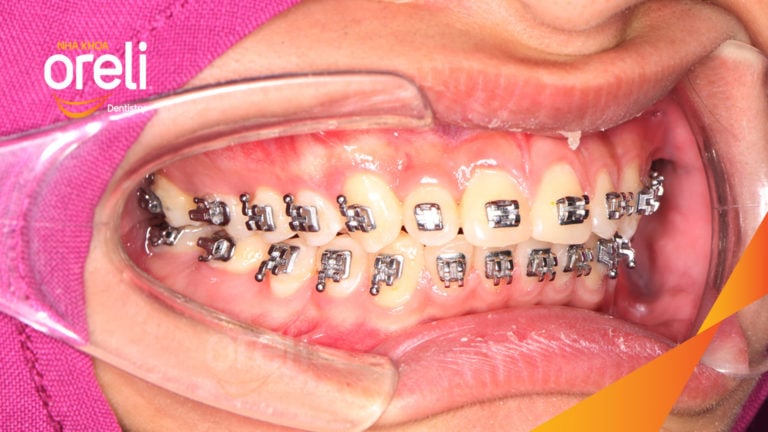

Ca niềng chỉnh chen chúc sai khớp cắn hạng 3 móm nhẹ – Kết quả thực tế ở Oreli Niềng răngChen chúcMóm Xem thêm